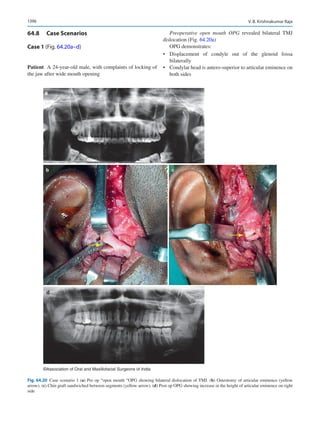

devised by the market and economics. The educational debt

for training our future generation is getting out of hand. In a

world where access to information is undoubtedly easier, the

cost of a formal education is skyrocketing. Alternate models

of education may arise disrupting this traditional model.

Apprenticeships of the Osler era may be aft. Centers of

excellence are likely to develop that allows a pathway of

nontraditional training to an interested and talented trainee.

Validation agencies like the International Board of

Certification of Oral and Maxillofacial Surgeons (IBSCOMS)